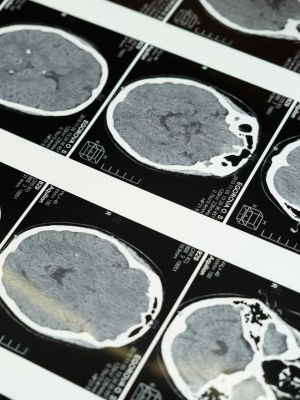

Neurologija takođe uključuje razumevanje i tumačenje slikovnih i električnih studija. Primeri korišćenih studija slikanja uključuju skeniranje kompjuterizovane tomografije (CT) i skeniranje magnetne rezonance (MRI) . Elektroencefalografija (EEG) se primenjuje radi analize električne aktivnosti mozga, posebno u dijagnostici poremećaja poput epilepsije. Pored toga, neurolozi koriste analizu cerebrospinalne tečnosti (CSF), prozirne tečnosti koja obavija mozak i kičmenu moždinu, kako bi dijagnostikovali infekcije nervnog sistema.

• Kompjuterska tomografija (CT), magnetna rezonanca (MRI), rendgenski snimci i ultrazvuk.

Kompjuterska tomografija (CT) je dijagnostički alat koji se koristi u identifikaciji i evaluaciji neuroloških poremećaja koristeći rendgenske zrake. Magnetna rezonanca (MRI) je izuzetno korisna u dijagnostici i praćenju neuroloških poremećaja. MRI omogućava detaljan prikaz struktura u mozgu i kičmenoj moždini, pružajući informacije koje su od suštinskog značaja za identifikaciju različitih neuroloških stanja.